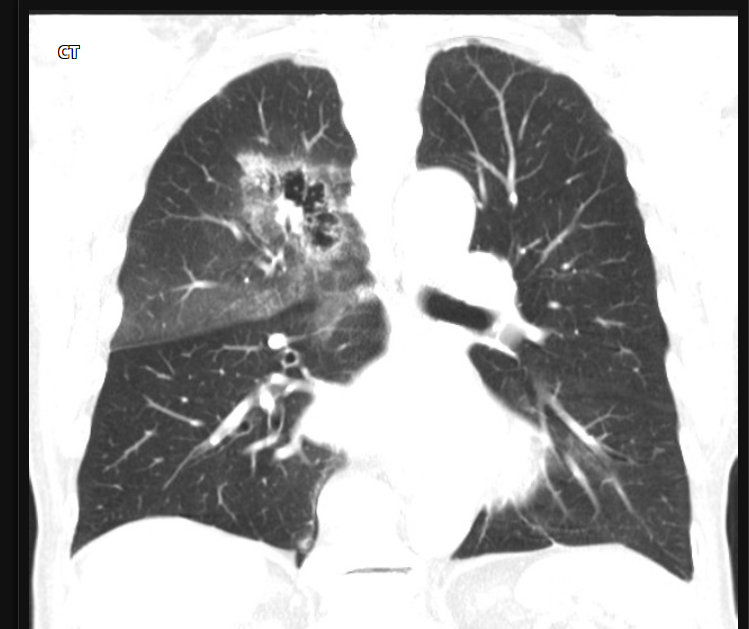

80 Mulher, Tosse

Consolidação com cavitação em lobo superior direito

Adenocarcinoma

Consolidação em lobo superior direito com áreas de cavitação

Padrão de micronódulos centrolobulares com árvore em brotamento

TB pós primária.